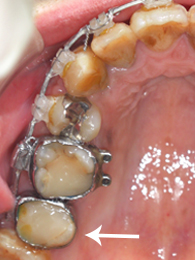

20代女性 右上7 奈良市在住

〔術前〕

虫歯が深く奥まであったので歯を抜かないといけないと思いましたが、根元の治療をしてもらい少ない歯だけでも残してもらいました。値段が高かったですが、白い被せ物にして大きな口で笑っても目立たなくて良かったと思います。